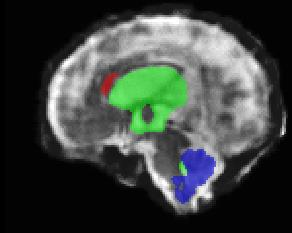

Limiting failures of machine learning systems is of paramount importance for safety-critical applications. In order to improve the robustness of machine learning systems, Distributionally Robust Optimization (DRO) has been proposed as a generalization of Empirical Risk Minimization (ERM). However, its use in deep learning has been severely restricted due to the relative inefficiency of the optimizers available for DRO in comparison to the wide-spread variants of Stochastic Gradient Descent (SGD) optimizers for ERM. We propose SGD with hardness weighted sampling, a principled and efficient optimization method for DRO in machine learning that is particularly suited in the context of deep learning. Similar to a hard example mining strategy in practice, the proposed algorithm is straightforward to implement and computationally as efficient as SGD-based optimizers used for deep learning, requiring minimal overhead computation. In contrast to typical ad hoc hard mining approaches, we prove the convergence of our DRO algorithm for over-parameterized deep learning networks with ReLU activation and a finite number of layers and parameters. Our experiments on fetal brain 3D MRI segmentation and brain tumor segmentation in MRI demonstrate the feasibility and the usefulness of our approach. Using our hardness weighted sampling for training a state-of-the-art deep learning pipeline leads to improved robustness to anatomical variabilities in automatic fetal brain 3D MRI segmentation using deep learning and to improved robustness to the image protocol variations in brain tumor segmentation. Our code is available at https://github.com/LucasFidon/HardnessWeightedSampler.